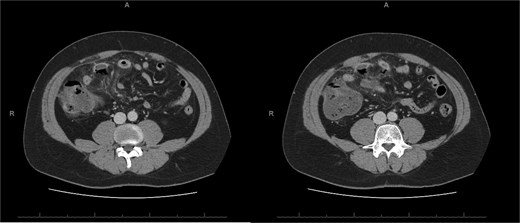

A 76-year-old female with a 3-day history of left upper abdominal pain, vomiting, and haematochezia. Her history included pulmonary embolism, multiple deep vein thromboses, with no ongoing anticoagulation, and an open partial colectomy for complicated diverticulitis a decade earlier. On admission, she was afebrile but tachycardic and showed localized tenderness in the left hypochondrium. Laboratory revealed leucocytosis with a white blood cell count (WBC) of 12 G/L, elevated C-reactive protein (CRP) of 46 mg/L, and hyperlactatemia of 2.6 mmol/l. Enhanced computed tomography (E-CT) revealed jejunal venous ischemia in the left upper quadrant, secondary to extensive porto-mesenteric thrombosis with reduced bowel wall enhancement, distention, and free intraperitoneal fluid (Fig. 1). She was managed conservatively with unfractionated heparin (UFH) with a bolus of 5000 U/l followed by 30 000 U/l/24 h (target INR 0.35–0.7), Piperacillin-Tazobactam, and bowel rest. After 48 h of monitoring in the intensive care unit (ICU), she exhibited marked biological and clinical improvement. E-CT on the third day showed restored bowel wall enhancement and stable porto-mesenteric thrombosis (Fig. 2). She was discharged on therapeutic low molecular weight heparin (LMWH) with enoxaparin sodium 120 mg every 12 h. At the 3-month follow-up, E-CT revealed near-complete thrombus resolution, without intestinal sequelae (Fig. 3).

Follow-up E-CT 72 h after conservative management in the first patient. Dashed arrows show improved viability of the small bowel with bowel wall enhancement. White arrows revealed the stability of the extended porto-mesenteric thrombosis.